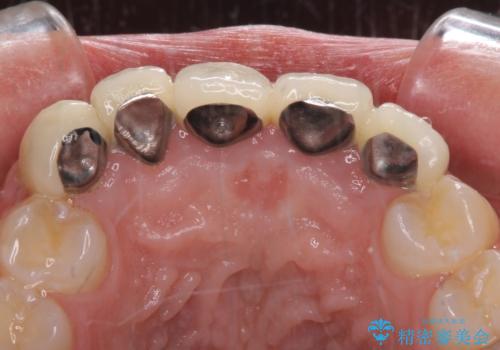

- 歯列不正を改善する目的で装着した前歯のセラミックが気になるとのことで来院された患者様です。

金属の裏打ちを用いたセラミッククラウンであったため歯肉縁に黒ずみが見えてくることは良くありますが、全体的に歯列が不揃いであることが気になったので、それらをオールセラミッククラウンにて改善することとしました。